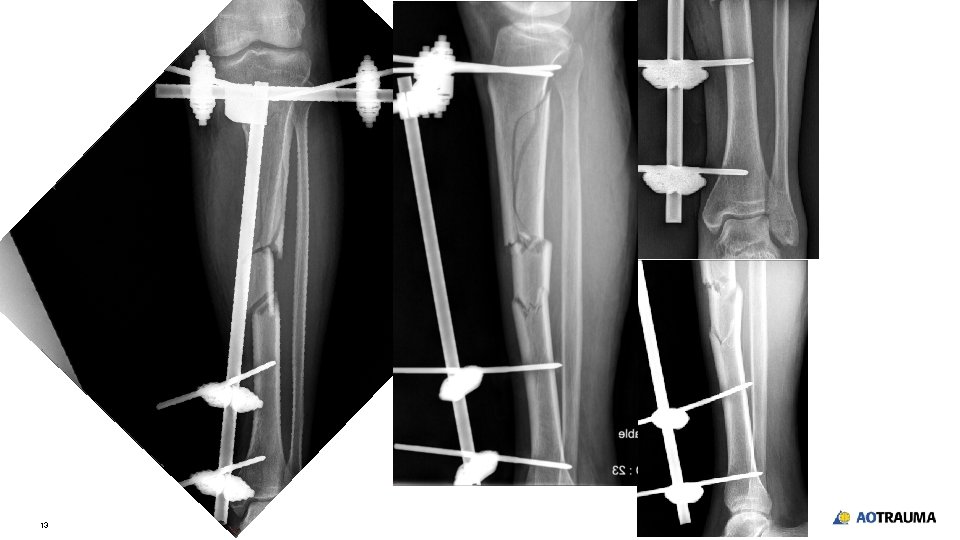

13

Take-home messages • • • 14 After resuscitation in multiple-fracture patients, secondary survey is important to have complete diagnosis Screening x-rays in every suspicious area X-ray should include the joint above and below the injured area Monolateral external fixation with modular technique is an effective and fast method to stabilize the fracture of long bones especially lower extremity Simple splint for upper extremity is acceptable in acute management in damage control orthopedics